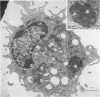

- Morris B., Moreno G., Bessis M. Ultrastructure des cellules DE LA LYMPHE AFF'ERENTE AUX GANGLIONS P'ERIPH'ERIQUES AVANT ET APR-ES STIMULATION ANTIG'ENIQUE. Nouv Rev Fr Hematol. 1968 Mar-Apr;8(2):145–154. [PubMed] [Google Scholar]